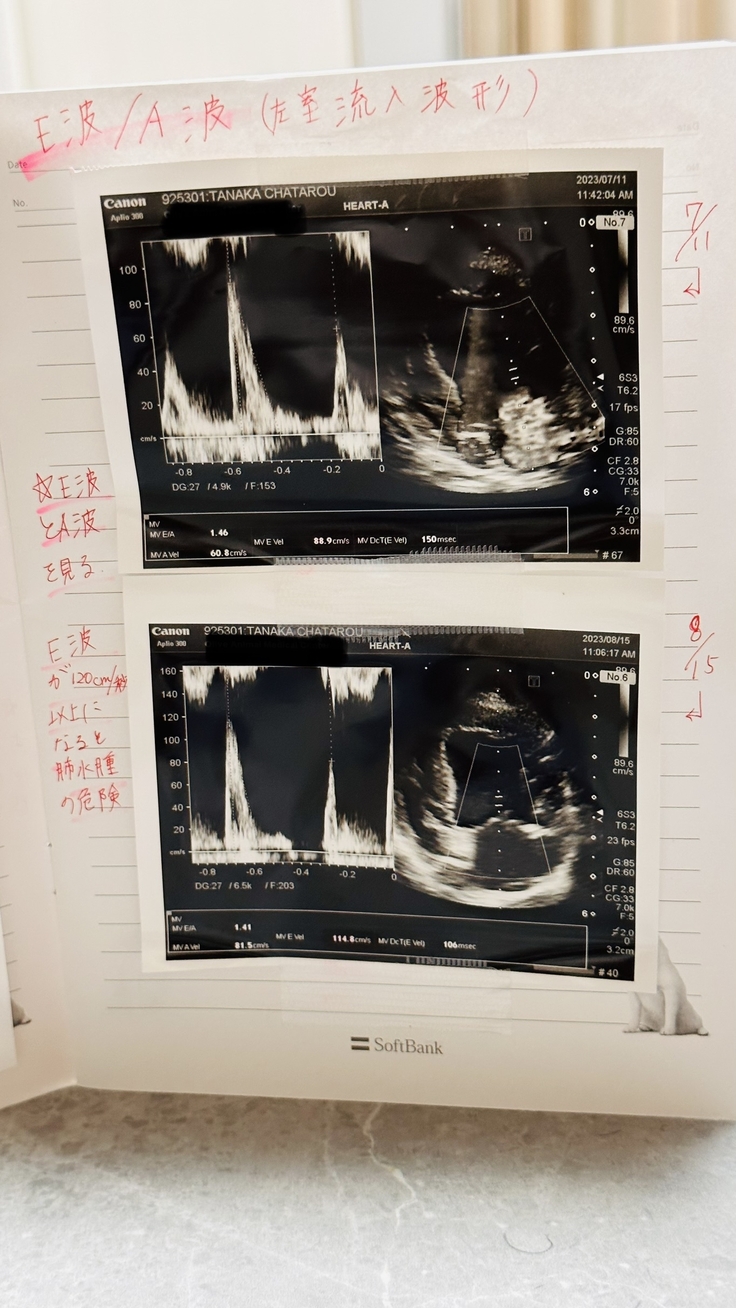

E波/A波(左室流入波形)*E波が120cm/秒 以上になると肺水腫の危険

こちらは前回よりも少し数値が高くなっていたため5%ほどお薬の量を増やし下がるようにしましょうとのこと。

前回7月→88.9cm/秒

今回8月→114.8cm/秒